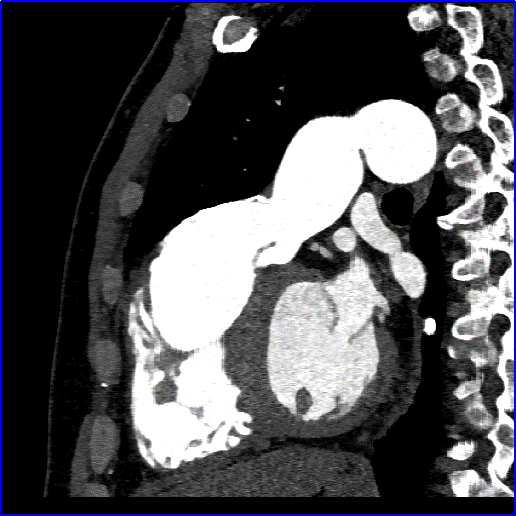

术前心脏CT评估

法洛四联症术后改变,室间隔、右室流出道前壁及肺动脉瓣水平多发片状钙化影。主肺动脉-右室流出道成角,肺动脉瓣形态欠规则。主肺动脉、左侧肺动脉干扩张,左肺动脉干直径约26mm;右位主动脉弓。右心房、右心室增大,右心室肌层增厚,心腔内未见明确充盈缺损影。冠状动脉左冠优势型,左主干起始段位于主动脉窦-主肺动脉之间,管腔未见显著狭窄。右心室流出道内径约36mm;主肺动脉瓣环内径约28mm;主肺动脉内径约38mm;主肺动脉发分叉处至右心室流出道长度约55mm。

术前增强CT图像显示肺动脉瓣结构损害